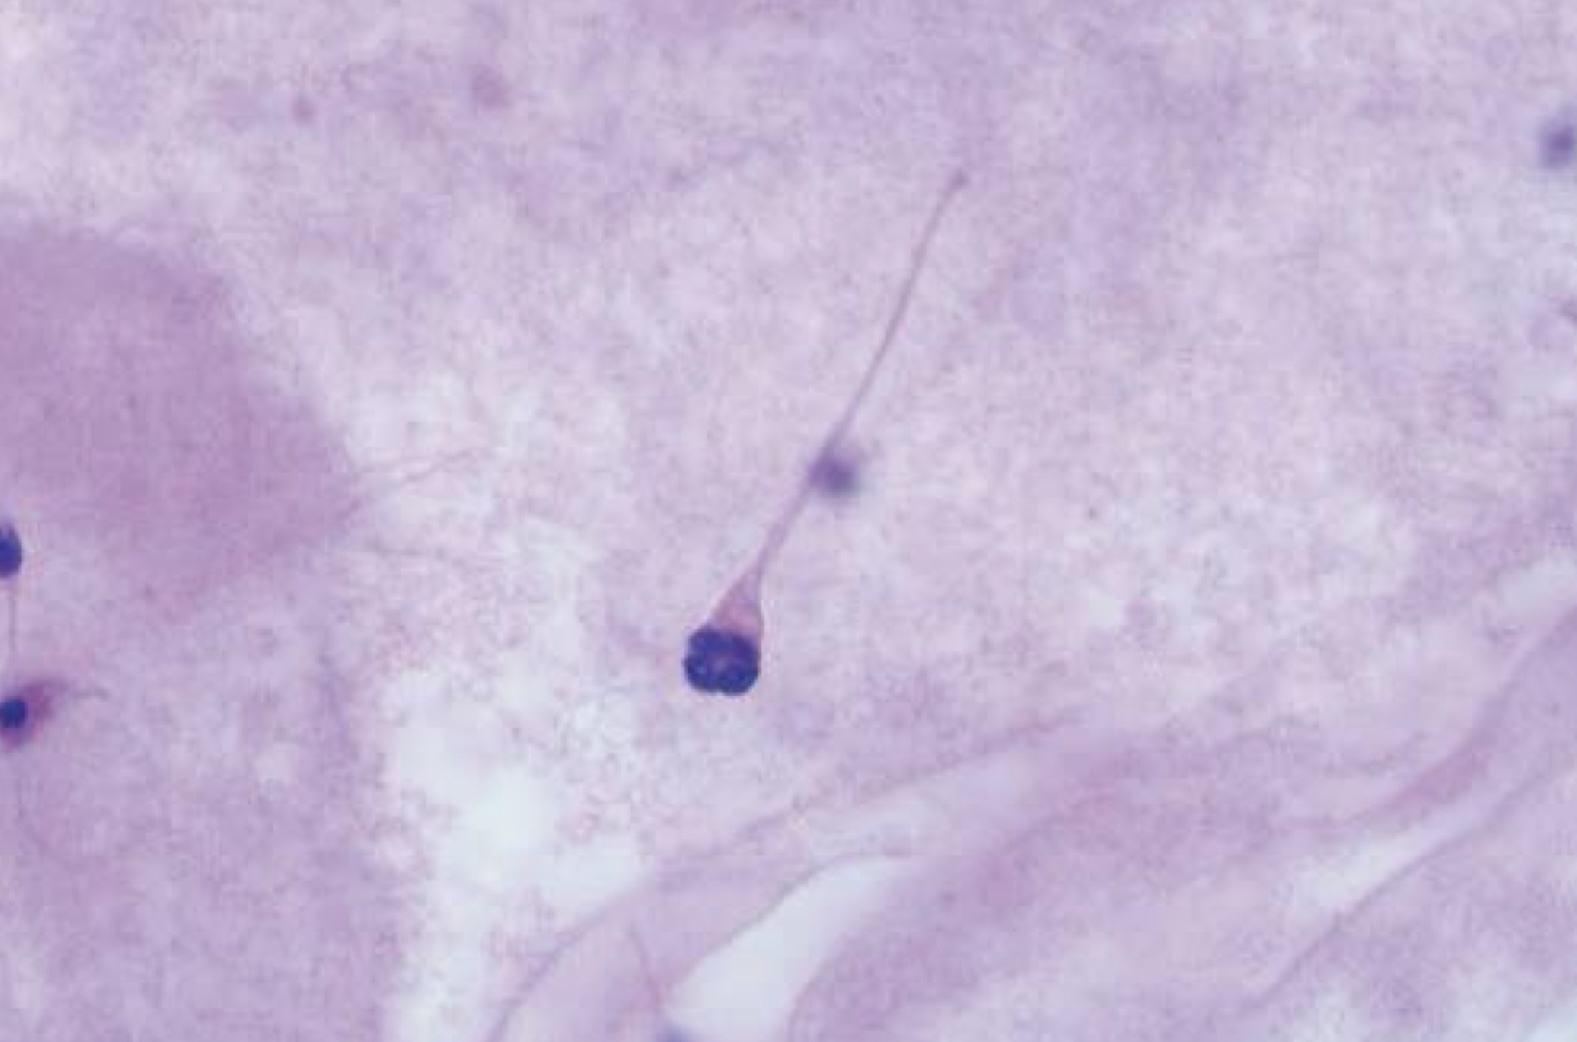

Spermatozoon with bent neck and spermatid

Spermatid